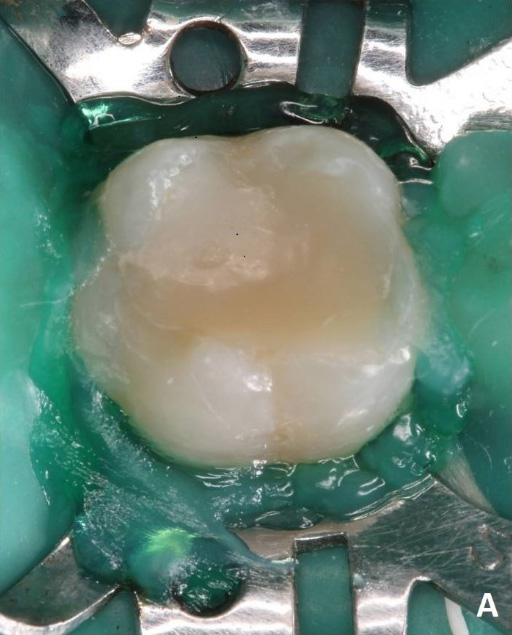

A 25-year-old female patient visited the Dental Hospital with a history of moderate spontaneous pain of short duration for 30 days in tooth 36, which had undergone endodontic treatment two years earlier.

Clinical (A) aspects of tooth 36.